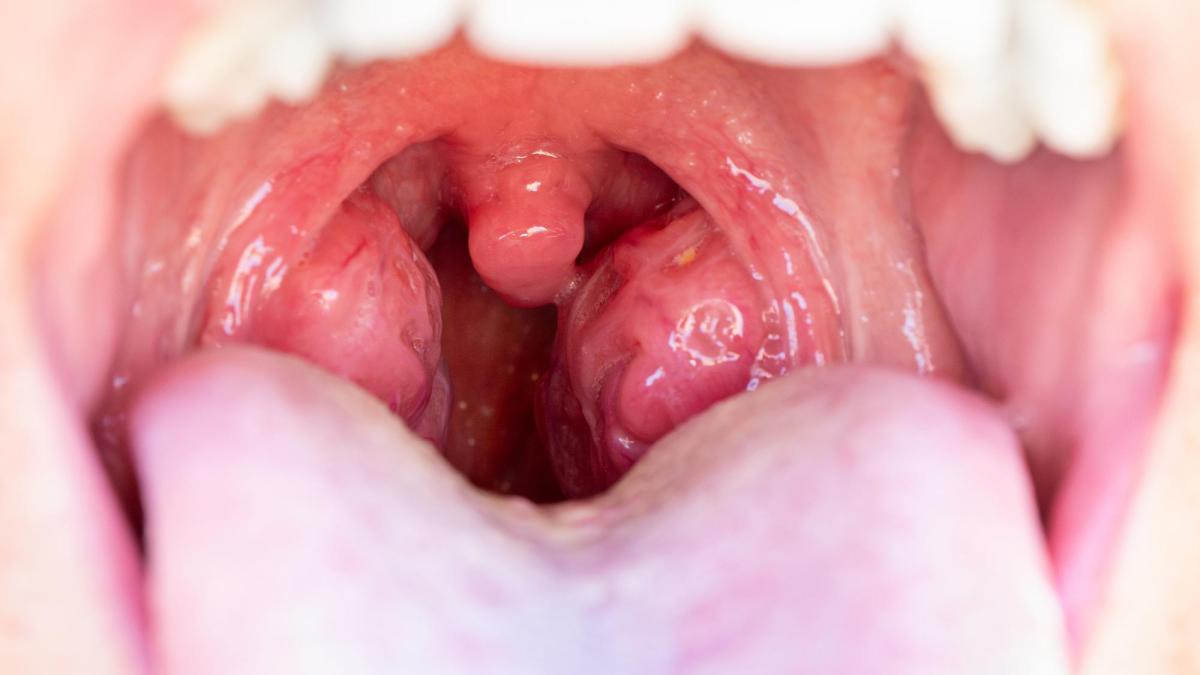

Amigdalita este inflamația amigdalelor, cele două formațiuni aflate în partea din spate a gâtului, cu rol esențial în apărarea organismului. Poate fi provocată de viruși sau bacterii (cel mai cunoscut fiind streptococul), iar recunoașterea timpurie a simptomelor ajută la un tratament corect.

- amigdale roșii și mărite (vizibile în oglindă)

- puncte sau depozite albe/gălbui pe amigdale (mai frecvent în amigdalita bacteriană)